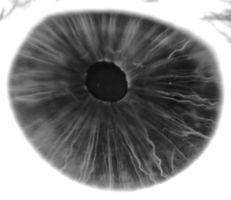

في البشر ومعظم الثدييات والطيور، القزحية ( Iris ؛ الجمع: قزحيات أو قزحية العين) عبارة عن هيكل حلقي رقيقة في العين ، المسؤولة عن السيطرة على قطر وحجم الحدقة وبالتالي كمية الضوء الوصول إلى شبكية العين . يتم تحديد لون العين من خلال القزحية. من الناحية البصرية ، البؤبؤ هو فتحة العين ، بينما القزحية هي الحجاب الحاجز .

القزحية تتكون من طبقتين: الطبقة الصبغية الليفية الوعائية الامامية المعروفة باسم سدى ، وتحت سدى خلايا الظهارية المصطبغة.

ترتبط السدى بالعضلة العاصرة ( العضلة العاصرة الحدقة )، والتي تنقبض الحدقة بحركة دائرية ، ومجموعة من العضلات الموسعة ( الحدقات الموسعة ) التي تسحب القزحية بشكل شعاعي لتكبير الحدقة وتسحبها في ثنايا.

السطح الخلفي مغطى بطبقة طلائية شديدة التصبغ بسماكة خليتين (ظهارة القزحية الصباغية) ، لكن السطح الأمامي لا يحتوي على ظهارة. هذا السطح الأمامي يظهر كعضلات موسعة. يمنع المحتوى الصبغي العالي الضوء من المرور عبر القزحية إلى الشبكية ، مما يقيده على الحدقة..[1] الحافة الخارجية للقزحية ، والمعروفة باسم الجذر ، متصلة بالصلبة والجسم الهدبي الأمامي. تُعرف القزحية والجسم الهدبي معاً باسم العنبية الأمامية. يوجد أمام جذر القزحية المنطقة التي يشار إليها باسم الشبكة التربيقية trabecular meshwork، والتي من خلالها يتم تصريف الخلط المائي باستمرار من العين، مما يؤدي إلى أن أمراض القزحية غالبًا ما يكون لها تأثيرات مهمة على الضغط داخل العين intraocular pressure وبشكل غير مباشر على الرؤية. توفر القزحية جنبًا إلى جنب مع الجسم الهدبي الأمامي مساراً ثانوياً لتصريف الخلط المائي من العين.

تنقسم القزحية إلى منطقتين رئيسيتين:

- المنطقة الحدقة pupillary zone هي المنطقة الداخلية التي تشكل حافتها حدود الحدقة.

- المنطقة الهدبية ciliary zone هي بقية القزحية التي تمتد إلى أصلها في الجسم الهدبي.

الطويق collarette هو أسمك منطقة في القزحية، تفصل الجزء الحدقي عن الجزء الهدبي. الطويق هي بقايا طلاء الحدقة الجنيني..[1] يتم تعريفه عادةً على أنه المنطقة التي تتداخل فيها العضلة العاصرة مع العضلة الموسعة. تمتد الحواف الشعاعية من المحيط إلى منطقة الحدقة ، لتزويد القزحية بالأوعية الدموية. جذر القزحية هو أنحف واكثر طرفية.[2]